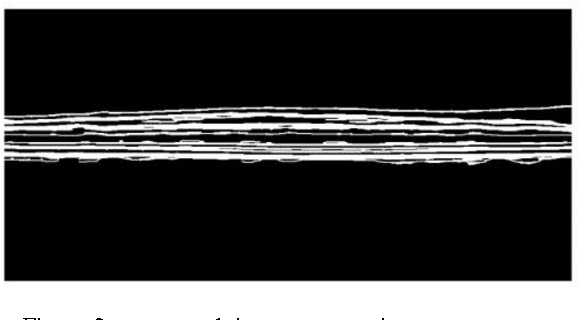

Quantification of intra-retinal boundaries in optical coherence tomography (OCT) is a crucial task for studying and diagnosing neurological and ocular diseases. Since manual segmentation of layers is usually a time consuming task and relay on user, a lot of attempts done to do it automatically and without interference of user. Although for extracting all layers usually same procedure is applied but finding the first layer is usually more difficult due to vanishing it in some region specially close to Fobia. To have a general software, beside using common methods like applying shortest path algorithm on global gradient of image, some extra steps are used here to confine search area for Dijstra algorithm especially for the second layer. Results demonstrates high accuracy in segmenting all present layers, especially the first one that is important for diagnosing issue.